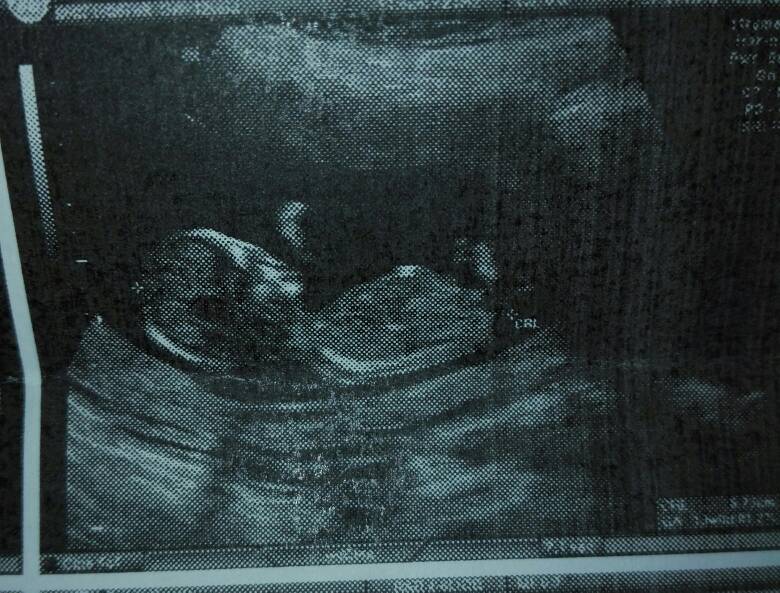

Ale ale wracajac do prenatalnych to wszystko jest w najlepszym porządku [emoji7][emoji7][emoji7] mamy zdrowa dzidzie, 6,6cm szczęścia [emoji7][emoji7][emoji7]wszystkie ryzyka niskie wiec cudownie, dzidzia skakala, machala rączkami [emoji7]

No i jednak zapytalam o płeć [emoji85] wedlug lekarza który jak sam mówi robi to od 10lat i rzadko zdarzają mu sie pomylki [emoji85] na takie 93% bedzie ..... dziewczynka [emoji173][emoji173][emoji173]Zobacz załącznik 920062